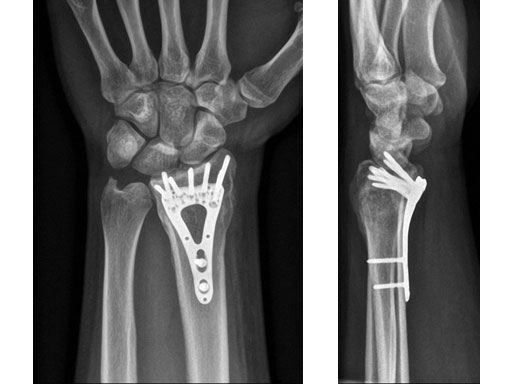

Fig 1ab Preoperative x-rays.

Fig 2ab X-rays postoperatively.

Fig 3ab X-rays 5 months postoperatively.